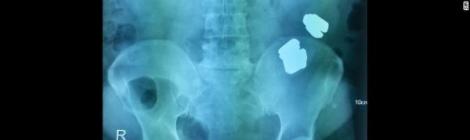

Detiene Policía Federal a persona con cápsulas de droga en su estómago

Por: Redacción Elementos de la Policía Federal (PF) detuvieron a una persona de origen mexicano procedente de Colombia en la Terminal 2 del Aeropuerto Internacional de la Ciudad de México […]